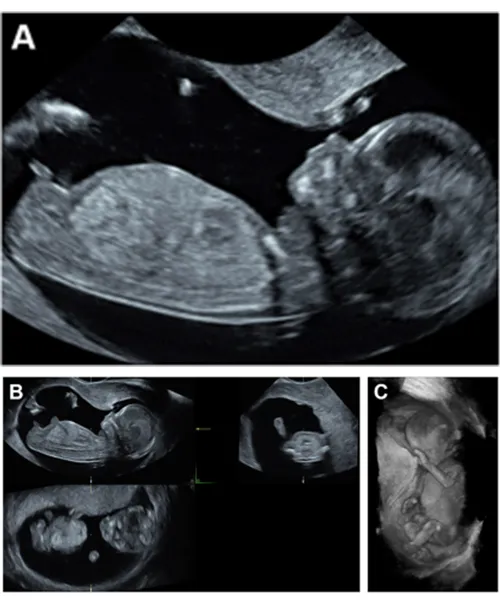

Fetal Neurosonogram